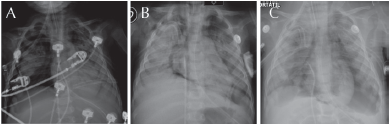

Terapia intensiva: evolucionó con incremento de parámetros ventilatorios con Peep 15, Pip 30, FR 55 pm, FiO2 100%, oximetría 93% e inestabilidad hemodinámica con saturación venosa central de 57%, acidosis respiratoria y síndrome de dificultad respiratoria aguda secundaria a neumonía nosocomial. Se incrementó la cobertura antibiótica a cefepime más vancomicina. Se presentó neumotórax bilateral secundario a barotrauma y se insertaron sondas pleurales bilaterales conectadas a sello de agua y succión negativa, fuga aérea persistente, se agregaron extrasístoles ventriculares con imagen de bloqueo de rama derecha y ecocardiografía con hipertensión pulmonar moderada (44 mmHg) secundario al daño pulmonar, se aportó apoyo inotrópico con milrinona, acidosis respiratoria persistente con parámetros ventilatorios para iniciar ventilación de alta frecuencia oscilatoria VAFO (no se pudo contar con el mismo), presentó paro cardiorrespiratorio con respuesta a la reanimación avanzada a los 6 minutos (Figura 2A).

Presentó un segundo paro cardiorrespiratorio que respondió a reanimación avanzada de 5 minutos, evolucionó con datos de tamponamiento cardíaco y por punción guiada por ecocardiografía se obtuvo aire y sangre escasa, con fracción de eyección ventricular de 15% se agregó adrenalina y dobutamina a la terapia inotrópica, persistió la fuga aérea con neumotórax y neumomediastino por barotrauma, evolucionó a falla orgánica múltiple con un tercer paro cardiorrespiratorio que no respondió a las maniobras de reanimación avanzada (Figuras 2B y 2C).